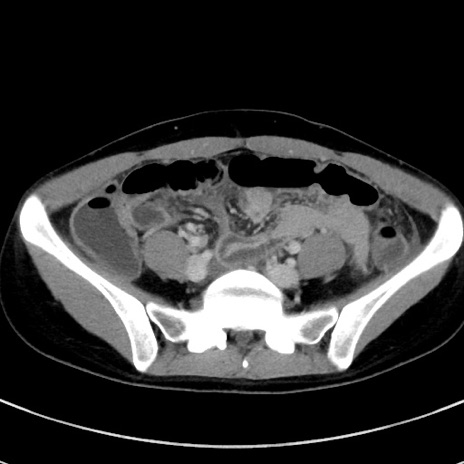

症例17(横断像)

【症例】20歳代女性

【主訴】嘔吐、下腹部痛

【現病歴】昨日夕食後に嘔吐し下腹部痛が出現。本日になっても嘔吐持続し改善しないため来院。

【身体所見】意識清明、BT 37.2℃、BP 108/67mmHg、腹部:平坦、やや硬、下腹部正中から右にかけて圧痛あり、反跳痛軽度あり、tapping pain(+)。

【データ】WBC 13600、CRP 14.94